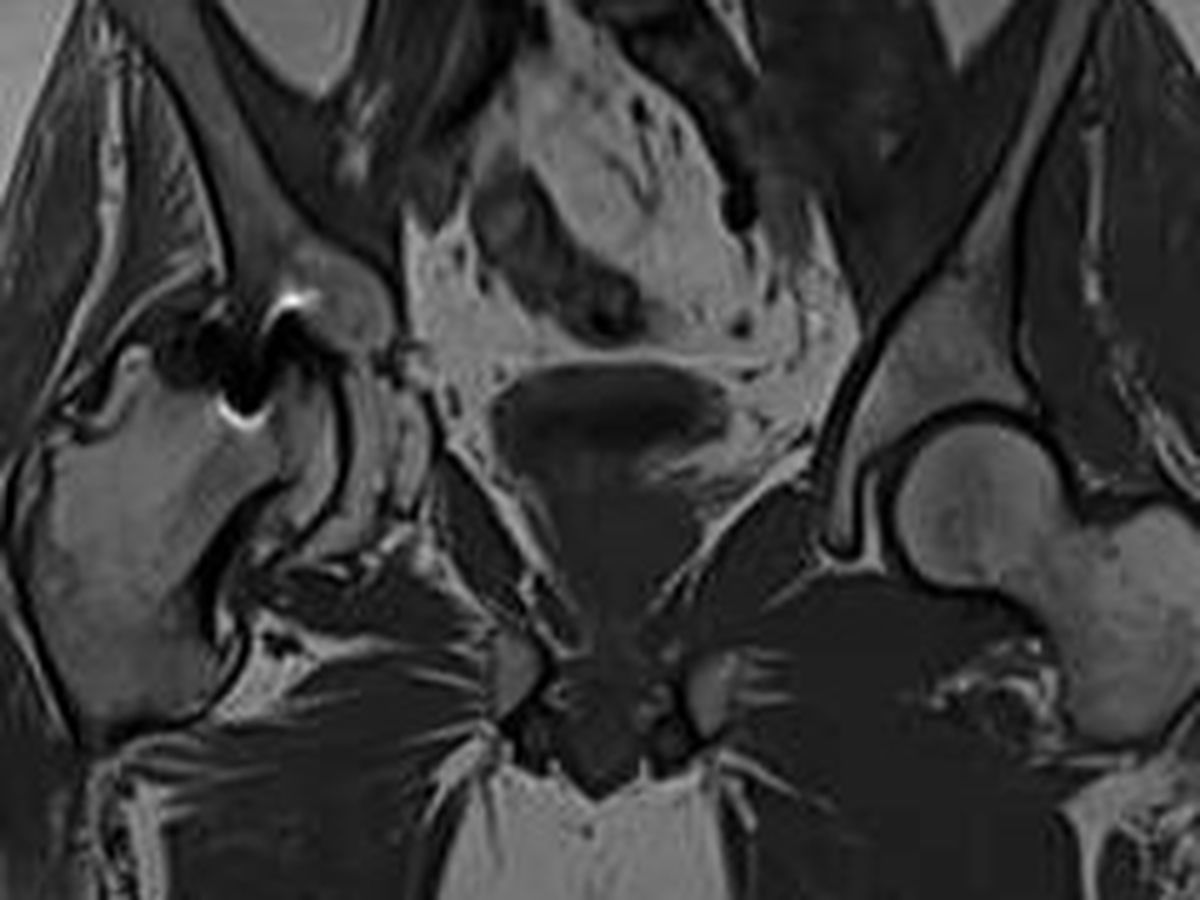

Yesterday, we finally saw why. The MRI revealed something devastating: there is absolutely no cartilage left in Zach’s hip. None. The hip ball is severely damaged and deteriorated. It is completely bone on bone. Severe arthritis has eaten away much of the joint. Fragments of bone are floating around in his body. The image is honestly hard to look at. The hip on the right side of the photo is his normal hip. Now look at the deterioration and malformation and disfigurement of the hip on the left side of the photo. There is virtually no "ball" socket left and the entire hip is severely deformed.